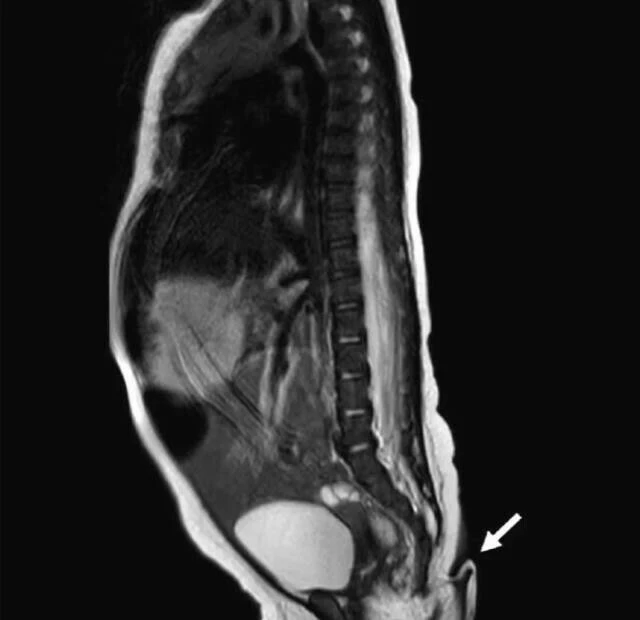

"Paediatric Surgery Case Reports dergisine konuşan Dr. Josue Rueda, Meksika'da bir ilk olan kuyruklu bebeğin kuyruk sokumundan çıkan deri parçasını, "3 ila 5 mm çapında ve 5,7 cm uzunluğunda, yumuşak, ince tüylerle kaplı ve sivri bir uca sahip. Acı çekmeden pasif olarak hareket ettirilebiliyor ancak spontane hareket gösteremiyor" sözleriyle anlattı.

Araştırmalara göre, Meksikalı bebeğin omurgası düzgün bir şekilde oluşmadı bu sebeple kuyruk meydana geldi. Bebeğin yeni doğduğu sırada beyin, kalp, işitme ve idrar testlerine girdiği, gayet sağlıklı olduğu sadece kuyruğu sıkıştırılınca ağladığı belirtildi.

Kuyruğu inceleyen ekip, yumuşak dokulu yapının atardamar ve toplardamarlara sahip olduğunu belirledi. Gerçek kuyrukların son derece nadir görüldüğü kaydedilirken, 2017 yılına kadar sadece 195 vakanın tespit edildiği, en büyük kuyruğun 20 cm olduğu ifade edildi.

İnsan kuyruklarını bilim insanları yalancı ve gerçek kuyruk olarak ikiye ayırıyor. Kuyruğa benzeyen yalancı kuyruklar bir omurga problemi veya tümörden kaynaklanıyor. Gerçek kuyruklarda hayvan kuyrukları gibi kemik yerine kas, kan damarları ve sinir bulunuyor. Bu kuyrukların, anne karnında gelişen her embriyonun kuyruk sokumunda üretildiği ve daha sonradan kuyruk kemiğini oluşturmak için vücuda geri çekilen oluşumlardan geldiği düşünülüyor.